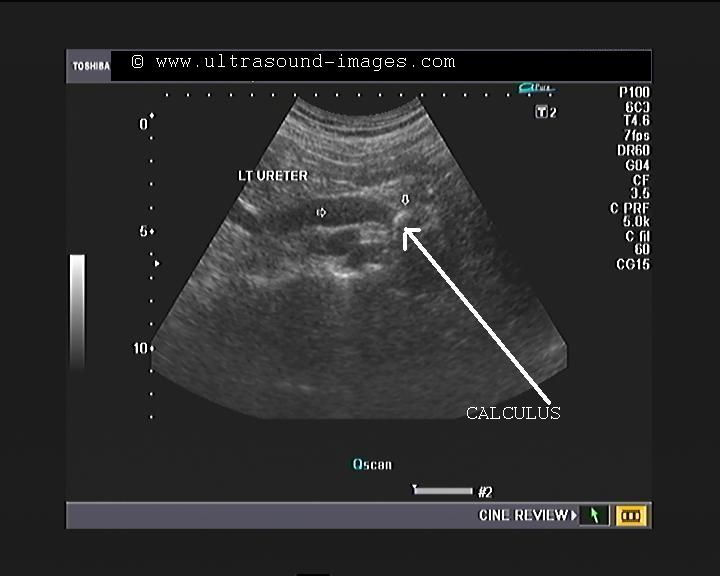

Mid ureteric calculus

(Calculi or stones in the mid ureter).

This patient had severe pain in the left lumbar region. Sonography of the left kidney and ureter shows moderately severe hydronephrosis in the affected kidney (ultrasound image top- left). The other ultrasound images show marked left hydroureter with dilation of the ureter till the level of the ureteric calculus. The stone in left ureter measures 1.2 cms. and causes severe backpressure changes on the upper urinary tract.